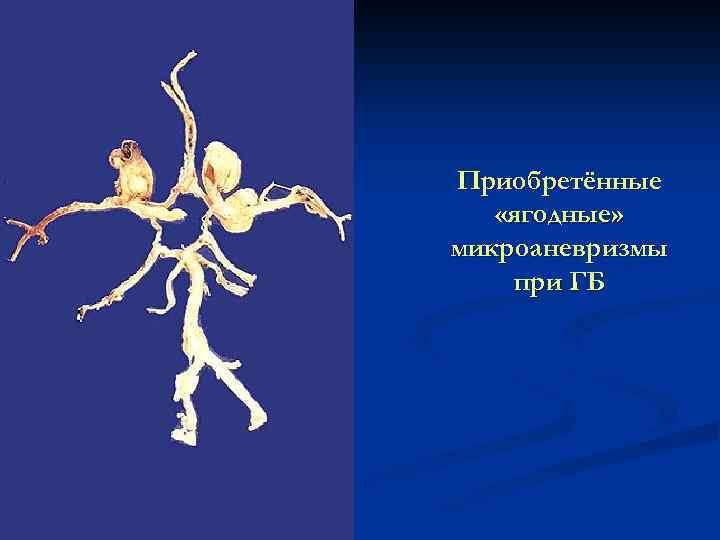

Приобретённые «ягодные» микроаневризмы при ГБ